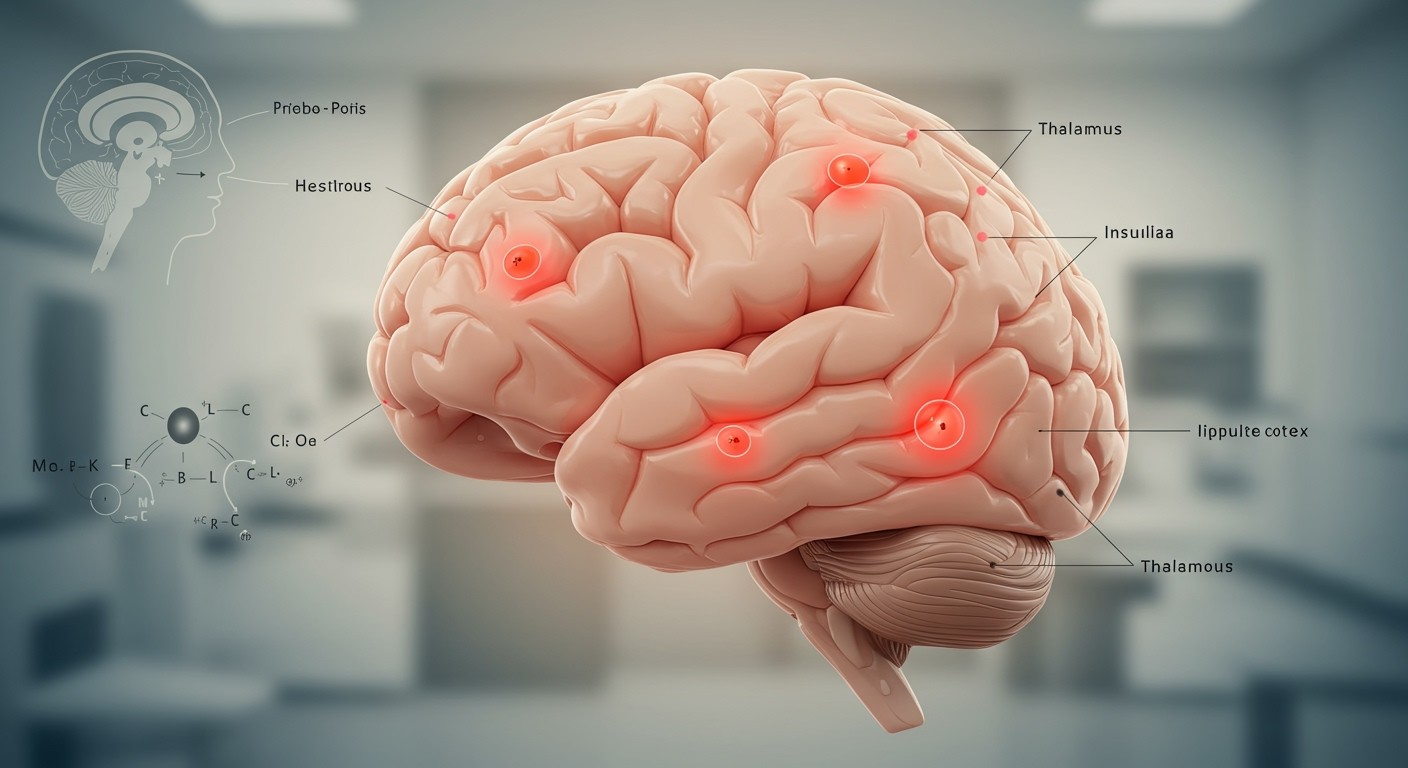

Az agy területei, amelyek részt vesznek a fájdalom feldolgozásában

Bár maga az agyszövet nem rendelkezik fájdalomreceptorokkal (nociceptorokkal), a fájdalomérzet feldolgozásában számos agyi terület játszik kulcsszerepet. Ezek a területek egy komplex hálózatot alkotnak, amely értelmezi a testből érkező fájdalomjeleket, és meghatározza azok intenzitását, helyét és érzelmi hatását.

Az egyik legfontosabb terület a thalamus. A thalamus a fájdalomjelek átkapcsoló állomása, ahonnan az információ továbbjut a kéreg különböző területeire. A thalamus nem csupán továbbítja a jeleket, hanem szűrőként is működik, befolyásolva, hogy mely jelek érik el a kéreg magasabb szintű feldolgozó központjait.

A szomatoszenzoros kéreg felelős a fájdalom lokalizálásáért és intenzitásának megítéléséért. Itt történik a fájdalom pontos helyének azonosítása a testen, és itt érzékeljük a fájdalom erősségét is. A szomatoszenzoros kéreg sérülése esetén a beteg elveszítheti a képességét a fájdalom pontos helyének meghatározására.

A fájdalom érzelmi komponensének feldolgozásában a limbikus rendszer játszik fontos szerepet. Ezen belül az amygdala felelős a fájdalomhoz kapcsolódó félelem és szorongás érzéséért, míg a hippocampus a fájdalmas élményeket tárolja a memóriában. Ezáltal a limbikus rendszer befolyásolja, hogy a fájdalom milyen érzelmi reakciót vált ki belőlünk, és hogyan emlékszünk vissza rá a jövőben.

A frontális kéreg, különösen a prefrontális kéreg, a fájdalom kognitív feldolgozásában vesz részt. Ez a terület felelős a fájdalommal kapcsolatos döntések meghozataláért, például arról, hogy hogyan reagáljunk a fájdalomra, vagy hogy milyen stratégiákat alkalmazzunk a fájdalom csillapítására. A frontális kéreg emellett befolyásolja a fájdalommal kapcsolatos figyelmünket és koncentrációnkat is.

- Insula: A test belső állapotának érzékelésében és a fájdalomhoz kapcsolódó érzelmek feldolgozásában vesz részt.

- Cinguláris kéreg: A fájdalom érzelmi és motivációs vonatkozásait dolgozza fel.

Ezek a területek komplex kölcsönhatásban állnak egymással, és együttesen határozzák meg a fájdalomérzetet. A fájdalomérzet nem csupán egy egyszerű idegi impulzus, hanem egy komplex pszichofiziológiai élmény, amely számos agyi terület együttes működésének eredménye.